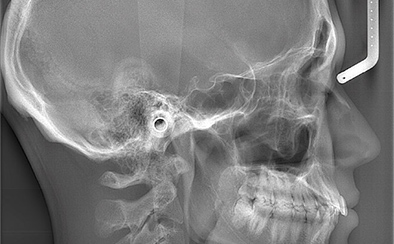

先端機器を用いて

精密検査・診断を実施

矯正治療では、治療前の精密検査や治療計画の作成、シミュレーションなどの準備が非常に重要です。当院は歯科用CT、セファロ、口腔内スキャナーなどの各種先端設備を導入しており、これらを活用して精度高くお口周りのデータを取得いたします。検査・診断結果をもとに、患者さんに適した治療計画を提案いたしますのでご安心ください。

セファロ

歯科用CT